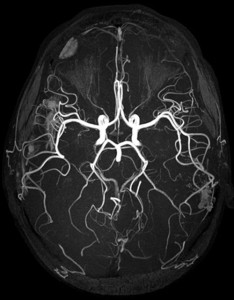

La risonanza magnetica è lo strumento diagnostico più utile per scovare la sclerosi multipla “perché è in grado di rilevare la presenza delle lesioni a livello encefalico-midollare e anticipare nei tempi giusti l’intervento del trattamento”.

“La risonanza magnetica grazie alla sua elevata risoluzione – continua l’esperto – permette di individuare la patologia al momento dell’esordio e così è possibile intervenire subito con la terapia più adatta. Ma non serve un abuso di questa diagnostica, basta un esame per scovare le lesioni nella corteccia e non solo nella sostanza bianca del cervello.

Può inoltre darci le misure oggettive della quantità di atrofia che si è sviluppata e la presenza delle microlesioni. Inoltre – conclude – da tempo è entrata nel monitoraggio di qualunque trial clinico di nuovi farmaci sperimentali per la sclerosi multipla verificandone l’efficacia”.